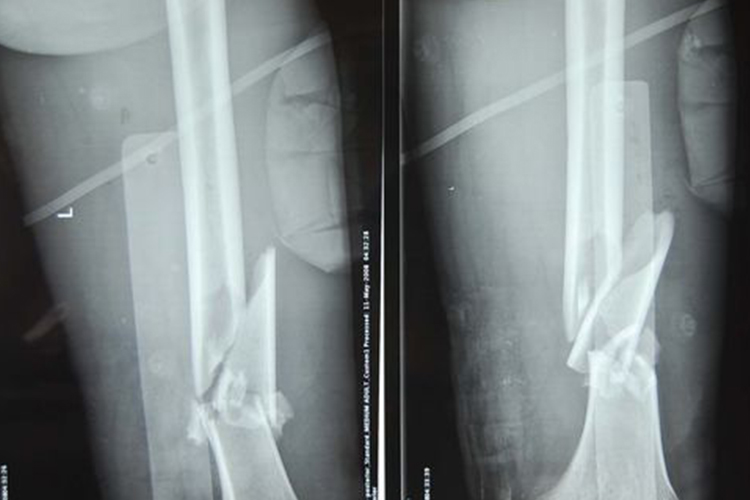

股骨干骨折

股骨干骨折的治疗可分为急救处理、外展板固定法、骨牵引法等。如果出现股骨干骨折,先就地行外固定处理,固定时略加牵引,即可减轻疼痛,又可部分复位。儿童股骨干骨折可用外展板固定法、骨牵引法;成人可应用骨牵引法以及切开进行复位治疗。